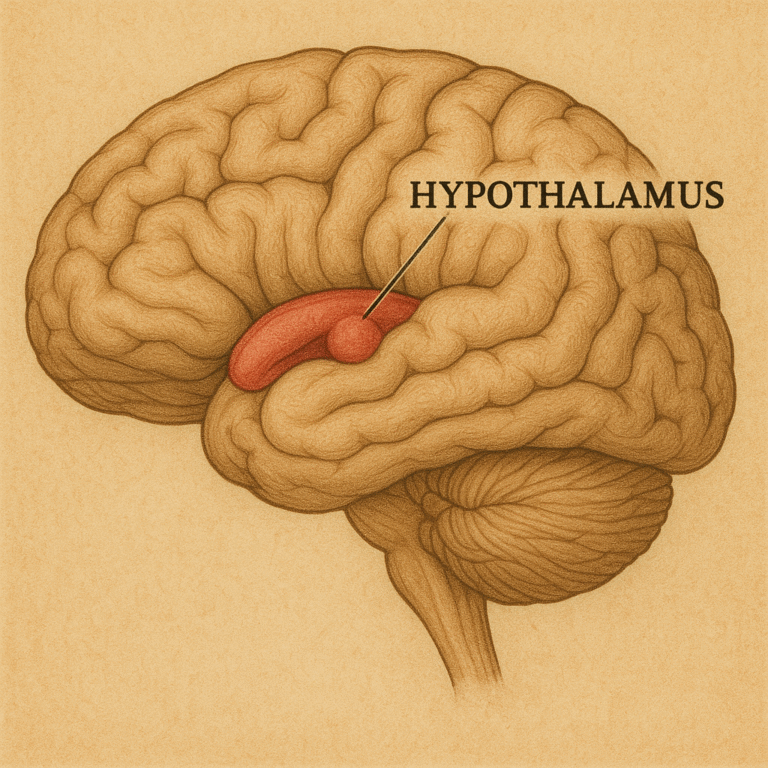

El Hipotálamo: Centro de Control de las Emociones y Punto de Encuentro entre Deseo y Voluntad

En el corazón del cerebro humano, entre los dos hemisferios, se encuentra…